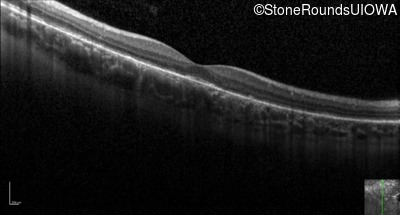

Optical Coherence Tomography - Right - 20/20 sc

Exemplar / OCT Stack